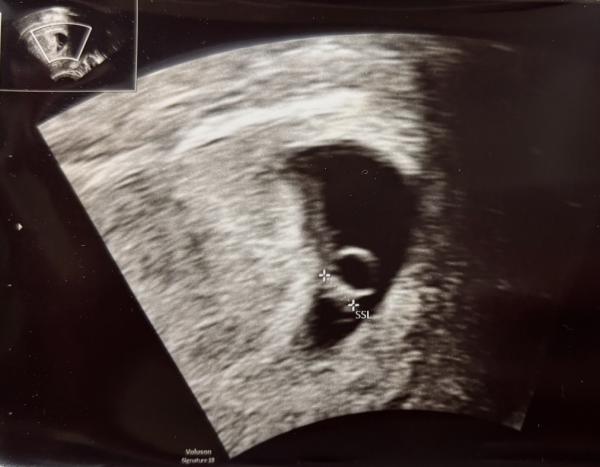

Hallo in die Runde, es ist meine 1. Schwangerschaft und somit bin ich mega gespannt und neugierig. Ich würde mich sehr über eure Ramzi-Einschätzung freuen, 6+2 vag. Ultraschall. Ich habe viel darüber gelesen, tue mir aber absolut schwer etwas abzuleiten von meinen Bild. Herzlichen Dank für einen Austausch 😊